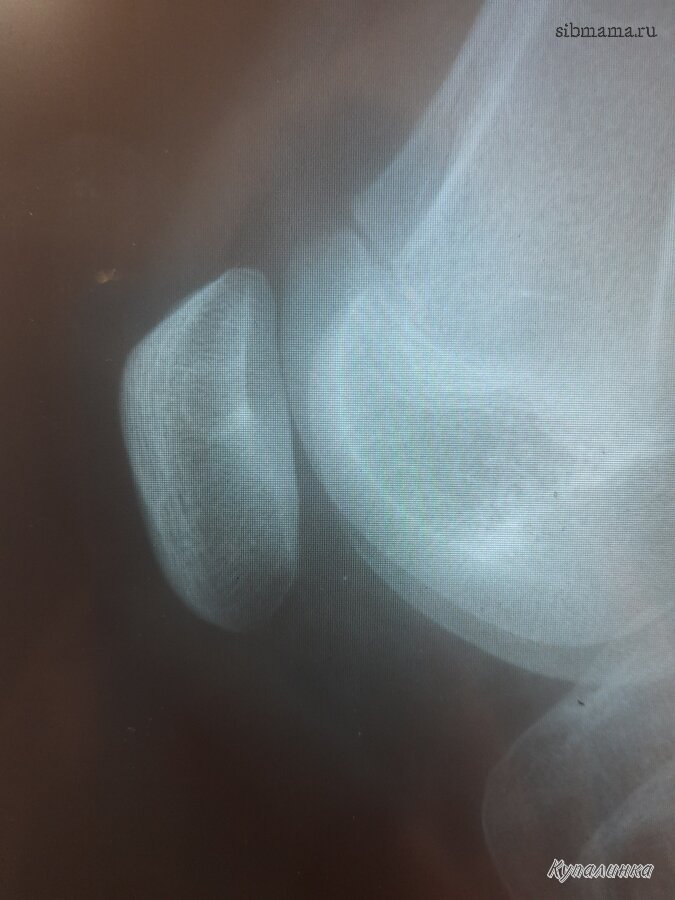

Купалинка писал(а):

Дочери 13 лет,болит левое колено,лечит ревматолог,отправил на рентген и на правом !!! колене обнаружили непонятно что. Что это может быть?

Какое мскт нужно сделать?какие анализы сдавать?

Инет по поиску остео-онколога дает отсылку к вам :-)

Здравствуйте.

МСКТ коленного сустава. Но лучше, сначала посмотреть ребёнка. Приходите.